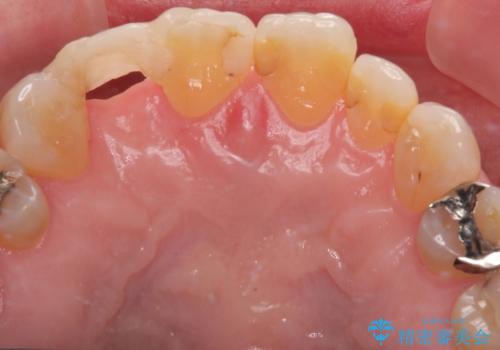

最新の症例

Latest cases